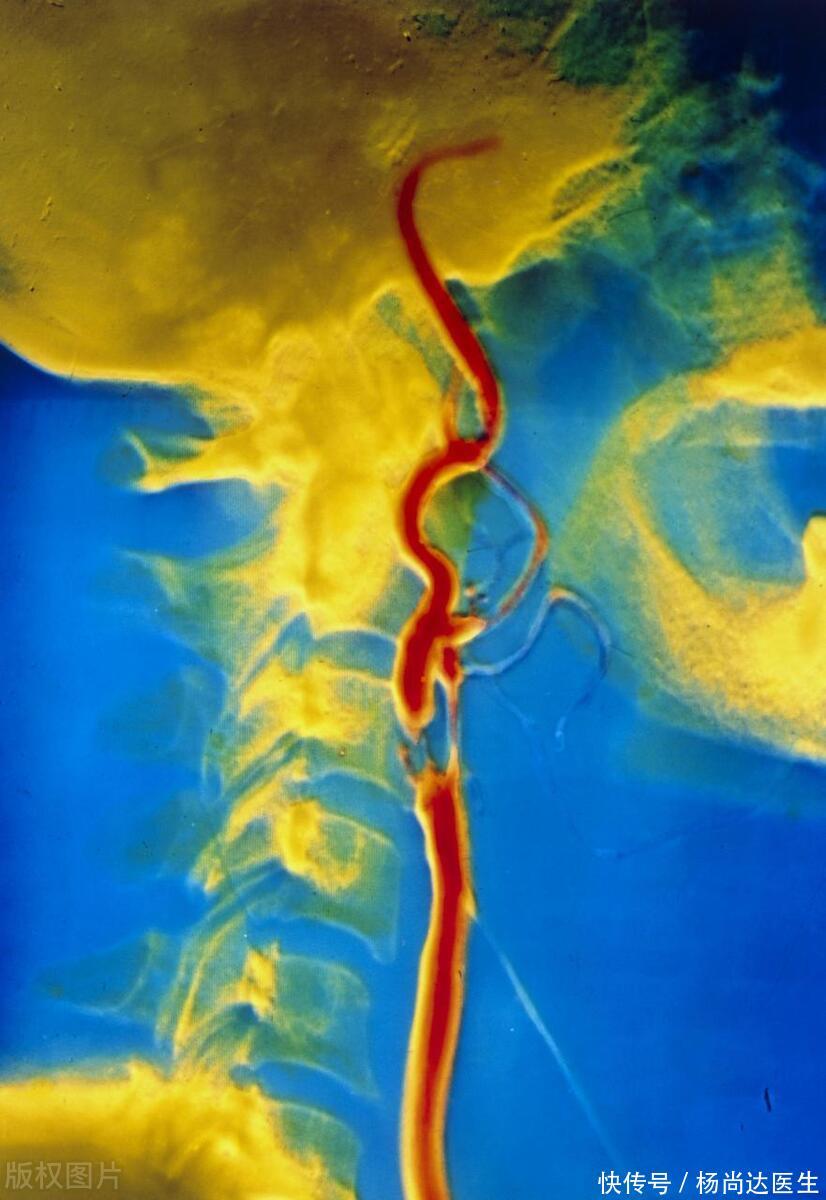

首先,我们得明白颈动脉斑块究竟是个什么东西。它就像是河流中的泥沙淤积,只不过这河流换成了我们身体内的颈动脉。岁月匆匆流逝,血液中的脂质、钙质等物质逐渐在动脉壁上缓慢积聚,最终酿成了我们熟悉的斑块。这些斑块会不断壮大,就像河道的淤积会不断加剧一样,最终可能导致血管狭窄,影响血液的正常流动。

首先,要看斑块的大小。报告通常会对斑块的大小尺寸进行详细描述,以提供更全面的信息。一般而言,斑块越大,对血流的影响就越显著,由此带来的风险也相应增加。这就像河道中的淤积,淤积越多,水流受阻的程度就越大。

其次,需要注意斑块的回声特性,这对于进一步评估动脉状况至关重要。在超声报告中,斑块通常以低回声、等回声、高回声或混合回声等形式描述。其中,低回声斑块往往意味着其内部成分较为松散,更易于脱落形成血栓,因此风险较高。这就像河道中的松散泥沙,一旦水流湍急,很容易被冲走形成泥石流。

再次,需要关注斑块的稳定性,这是评估动脉疾病严重程度和治疗方案的重要指标。稳定的斑块表面光滑,与血管壁贴合紧密,不易脱落;而不稳定的斑块则表面粗糙,容易破裂,形成血栓的风险也就更高。这就像河堤的稳固性,稳固的河堤能够抵御洪水的冲击,而松散的河堤则容易在洪水来临时崩塌。